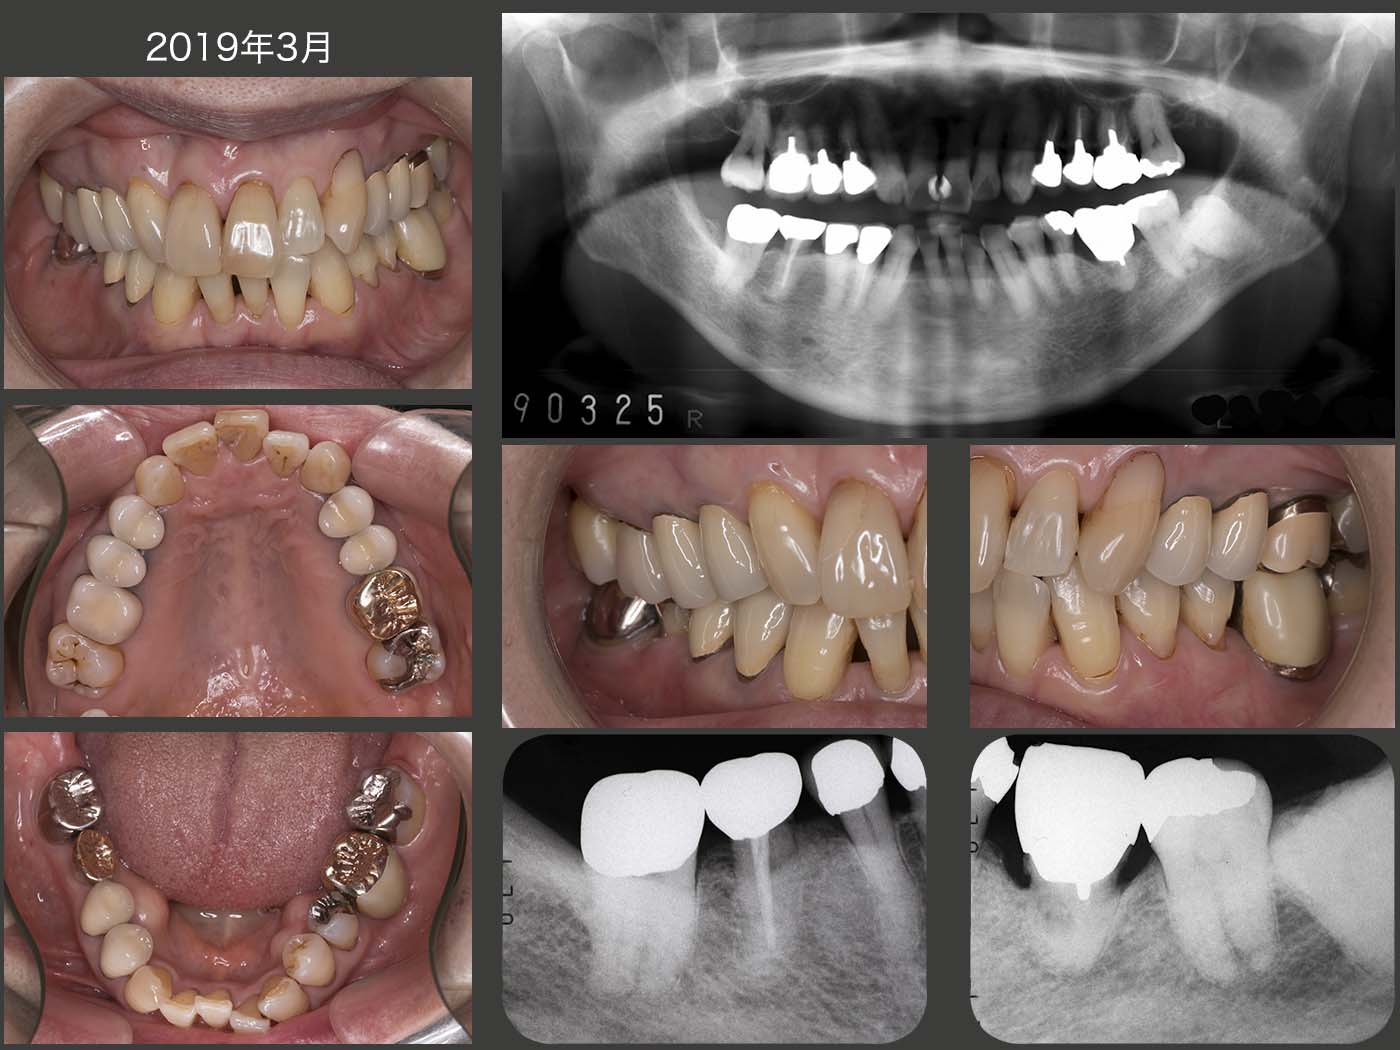

2019年3月の状態.移植された右下6は,ドナー歯が上顎側切歯であり,隣在歯と連結固定しなかったにもかかわらず,約19年間経過は良好である.一方,移植後約17年経過の左下6については,残念ながら置換性吸収が進行している.もうこのまま経過を観察するしか術がない.